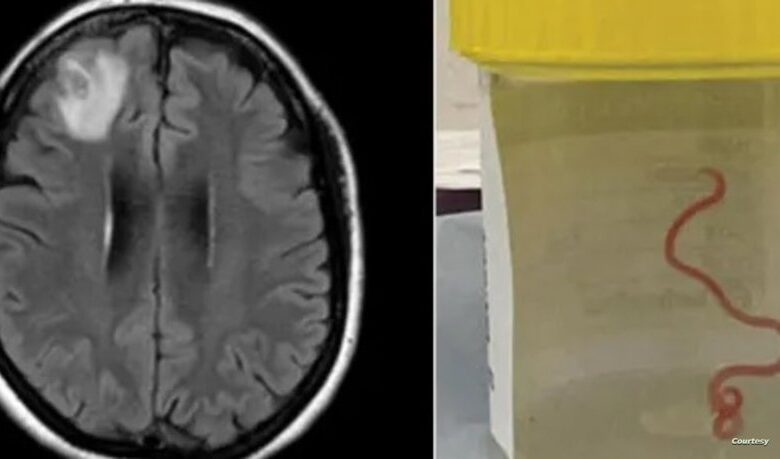

وسحبت جراحة الأعصاب، الدكتورة هاري بريا باندي، الدودة التي يبلغ طولها 8 سنتيمترات من المريضة، مما أصاب العاملين في المستشفى بالدهشة.

وعلى إثر ذلك، أدخلت مستشفى كانبيرا، حيث كشفت فحوص الرنين المغناطيسي لدماغها عن وجود تشوهات تتطلب عملية جراحية.

وعقد الفريق الطبي في المستشفى اجتماعا لمعرفة نوع الدودة، لكنهم لم يتمكنوا من تحديد ذلك، وتم إرسالها إلى أحد العلماء المتخصصين الذي أكد أنها دودة Ophidascaris robertsi التي تتواجد في الثعابين.